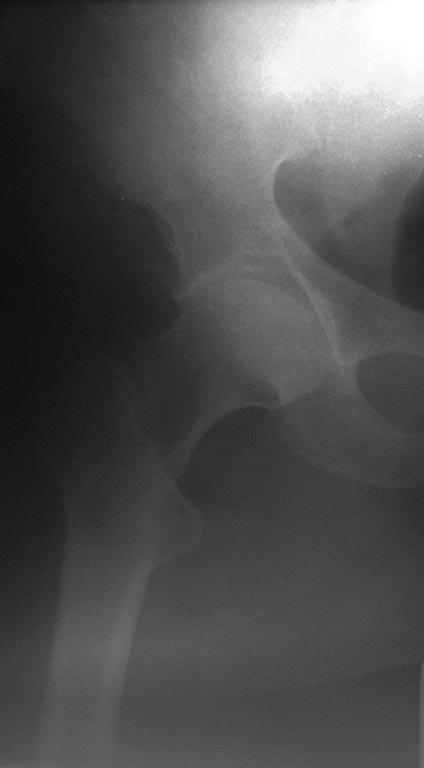

Добрый вечер уважаемые коллеги. На консультацию обратилась пациентка 62

лет с жалобами в области правого тазобедренного сустава, хруст и

ограничения движения в суставе.

Из анамнеза : 12 апреля 2016 года упала дома на область правого

тазобедренного сустава, доставлена в больницу, где больной было наложено

скелетное вытяжение, а 14 апреля 2016 года выполнена операция -

остеосинтез правого бедра, конструкция DHSA (Китай). Полтора-два месяца

находилась в горизонтальном положении, затем вертикализирована, начала

передвигаться при помощи ходунков с возрастающей нагрузкой на

оперированную конечность.

21 числа больной выполнен рентген контроль, больная отправлена на

консультацию к оперирующему хирургу, которым рекомендовано продолжить

возрастающую нагрузку и разработку движения в суставе. Больная

Прошу рассмотреть несколько вариантов лечения пациентки:

1. Согласиться с рекомендациями оперирующего хирурга (разработка

движения и возрастающая нагрузка),

2. Дождаться полной консолидации и удаления винта DHSA,

3. Убрать все в ближайшее время и костная пластика дефекта,

4. Убрать все в ближайшее время + костная АО-пластика + PFNA с аугментацией.